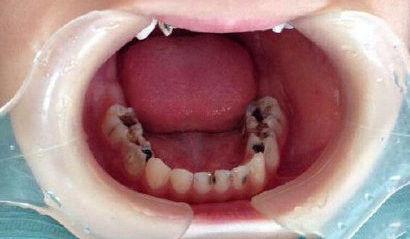

低龄儿童龋

这种同时累及前牙区多个乳牙的蛀牙,专业名称是早期(低龄)儿童龋(ecc)

dga技术适用于重度低龄儿童龋齿(secc)且无法配合常规牙科治疗的患儿